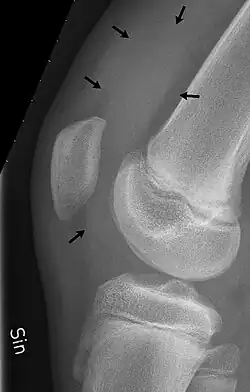

X-ray of the knee of a 12-year-old male, with knee effusion extending into the suprapatellar bursa.

1. the suprapatellar bursa or recess between the anterior surface of the lower part of the femur and the deep surface of the quadriceps femoris.[2] It allows for movement of the quadriceps tendon over the distal end of the femur. In about 85% of individuals, this bursa communicates with the knee joint. A distension of this bursa is therefore generally an indication of knee effusion.[3]